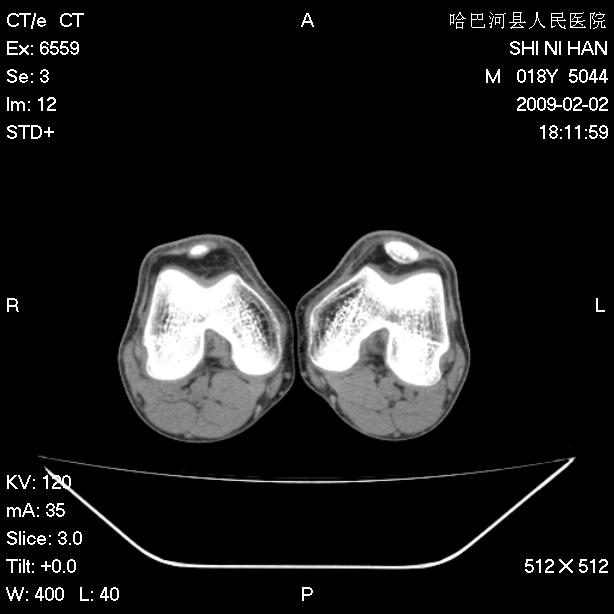

标题: CT17889:外伤后右膝关节反复疼痛3年余 [打印本页]

标题: CT17889:外伤后右膝关节反复疼痛3年余

ct未见明显异常。关节腔未见明显积液,半月板未见明显撕裂。但最好还是mri看看韧带及半月板情况。